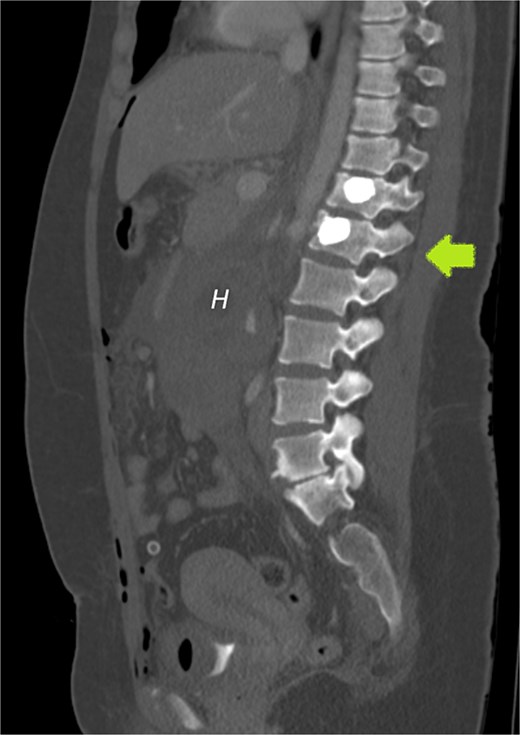

Our patient had an uneventful vaginal delivery, no abortions, no curettages, or tubal sterility. The patient’s only relevant history was of abdominal trauma during a traffic accident. A study by Cigerci et al found abdominal injuries to be present in as many as 23% of patients with traumatic thoracolumbar fractures [12]. The position of the gestational sac is just below the level of the fractured L1 vertebra (Fig. 7) could suggest an association of RPEP with previous abdominal trauma.

CECT of the abdomen and pelvis in the sagittal plane, bone window. Gestational sac (H for hematoma) was implanted just inferior to the level of a previous traumatic L1 vertebral fracture (arrow).